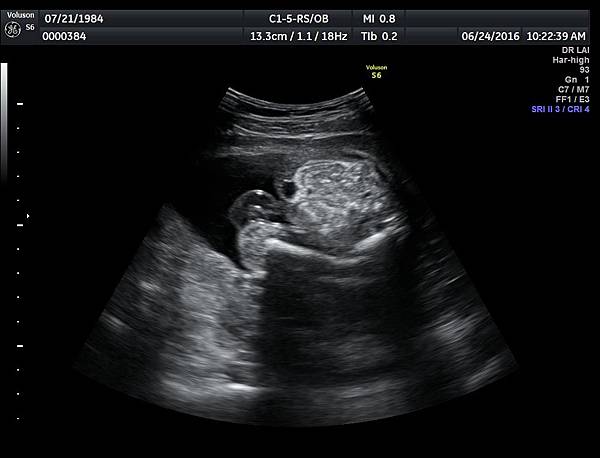

6月24日在我的診所,我幫一位懷孕22週31歲的孕婦看高層次超音波,發現胎兒的腸子很白,形狀也特別的怪( 附圖 1~12 ),我建議她做進一步相關的檢查,包括抽羊水檢查等等。